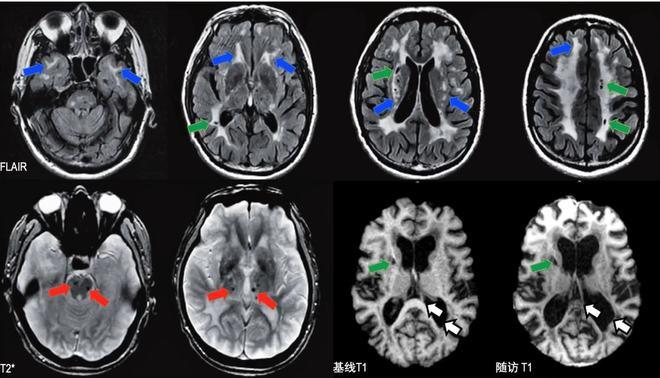

- 磁共振成像:MRI有非常典型的表现,即在脑白质(特别是颞叶白质)和基底节区域出现多发的小梗死灶和信号异常(白质病变)。